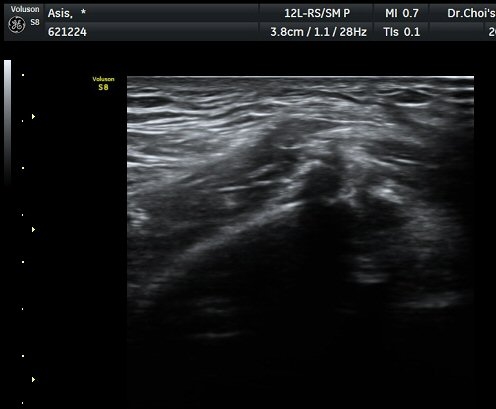

Àü»óÀå°ñ±ØÀÇ ºñ½ºµëÇÑ Á¾´Ü¸é°Ë»ç¿¡¼­ ¼­ÇýºÎ  Àδ밡 ºÎÂøµÇ´Â Àü»óÀå°ñ±ØÀÇ °ß¿­°ñÀýÀÌ

°üÂûµÇ°í(±×¸² 1) ¿ÜÃø´ëÅð±ÙÇǽŰæÀÇ ºÎÁ¾ÀÌ °üÂûµÊ(±×¸² 2, 3). Àü»óÀå°ñ±Ø Ⱦ´Ü¸é°Ë»ç¿¡¼­